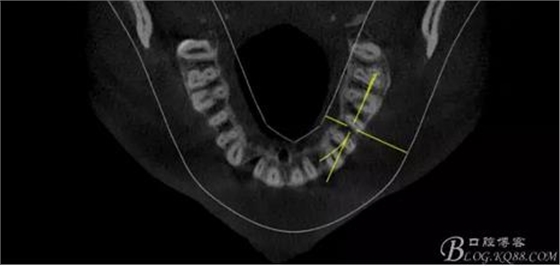

(1)檢查:12唇側(cè)牙齦可見竇道,牙體顏色較鄰牙暗,無光澤,形態(tài)完整無缺損,唇側(cè)及近遠(yuǎn)中向未提及牙周袋。腭側(cè)齦緣輕度紅腫,舌側(cè)窩可探及裂溝,可見浸墨狀痕跡,沿裂溝舌側(cè)探診牙周袋深大于11mm,除患牙外全口牙周狀況良好,為探及牙周袋,牙齦色粉紅。邊緣菲薄,質(zhì)地堅(jiān)韌。12冷熱診無反應(yīng),叩診(+-),無明顯松動(dòng),無咬合創(chuàng)傷。12根尖x線片示,根管中三分之一中可見一斜向線樣透射影像根尖區(qū)及遠(yuǎn)中根三分之一可見低密度透射暗影,錐形束CT示12根尖區(qū)唇腭向骨吸收已穿通,根面溝達(dá)根中三分之一卷曲分出另一牙根,再未見其他明顯的根管系統(tǒng)。